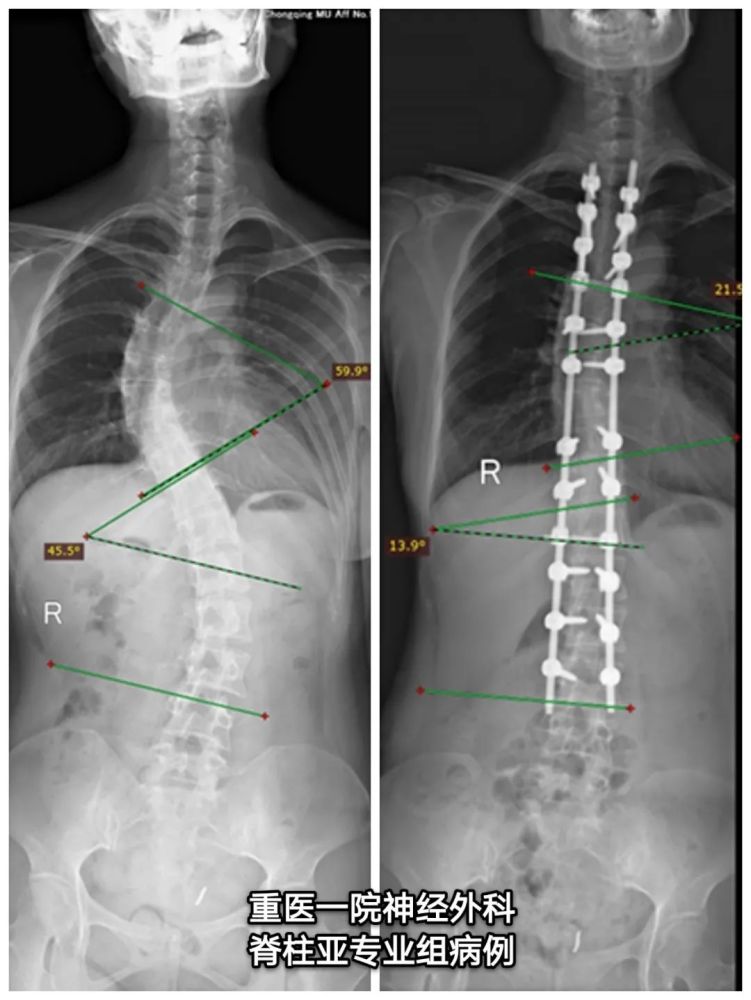

脊柱s型弯曲,脊柱s型弯曲图片

辅助检查:脊柱全长x线示脊柱侧弯畸形,胸椎左侧弯曲,腰椎右侧弯曲.

脊柱s型弯曲图片